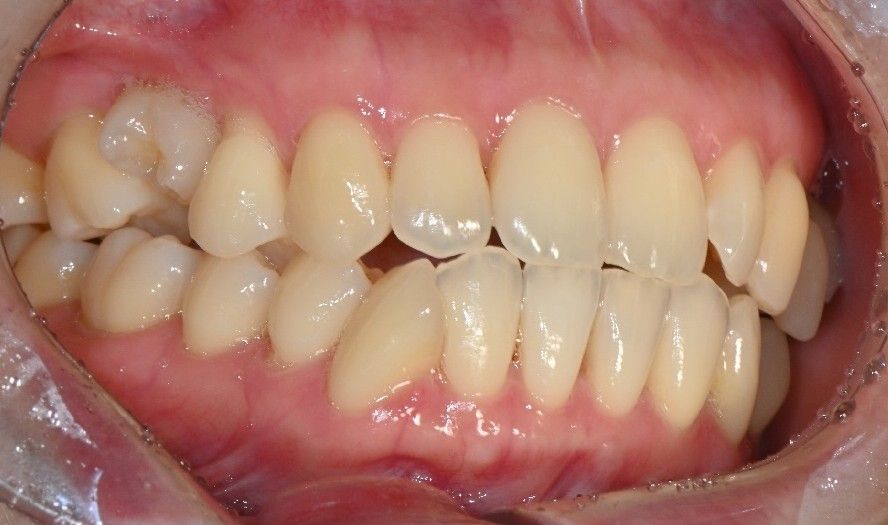

• 3번 째 사진

사진상으로는 특별히 문제가 보이지 않습니다. 치아의 문제가 아닌 신경에 문제가 있을수도 있습니다.

치아에 이상이 없는 상태에서도 통증이 있다면 치아에 과도한 힘이 가해지고 있을 가능성이 있습니다.

턱관절 질환은 주로 턱에 가해지는 힘이 강할때 생기는데 턱관절에 힘이 가해지는 순간에 치아에도 힘이 가해지게 됩니다.